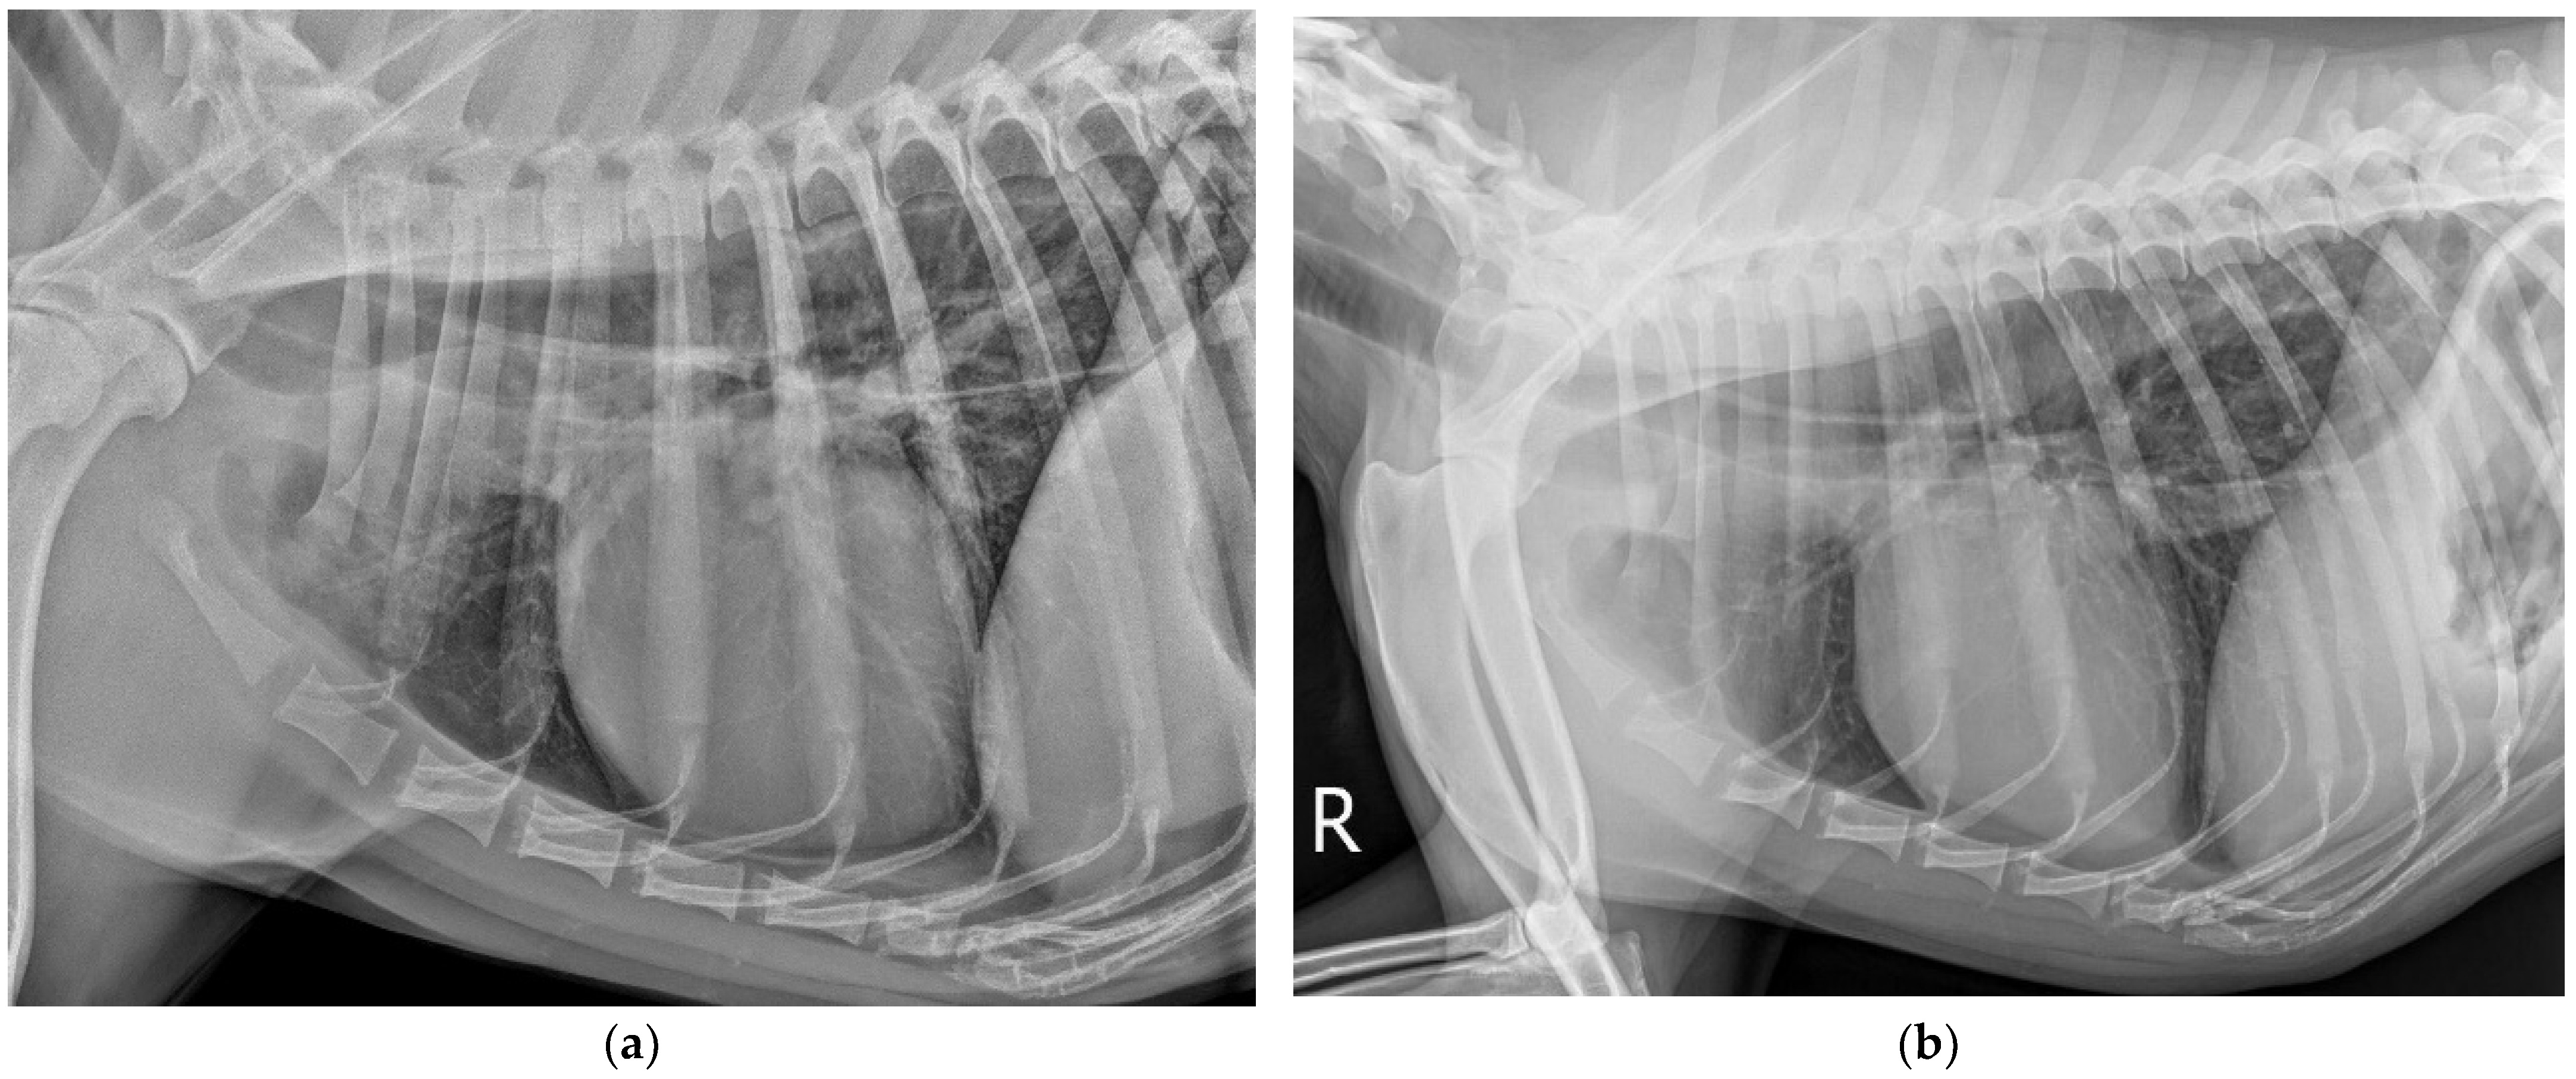

2. Case Description